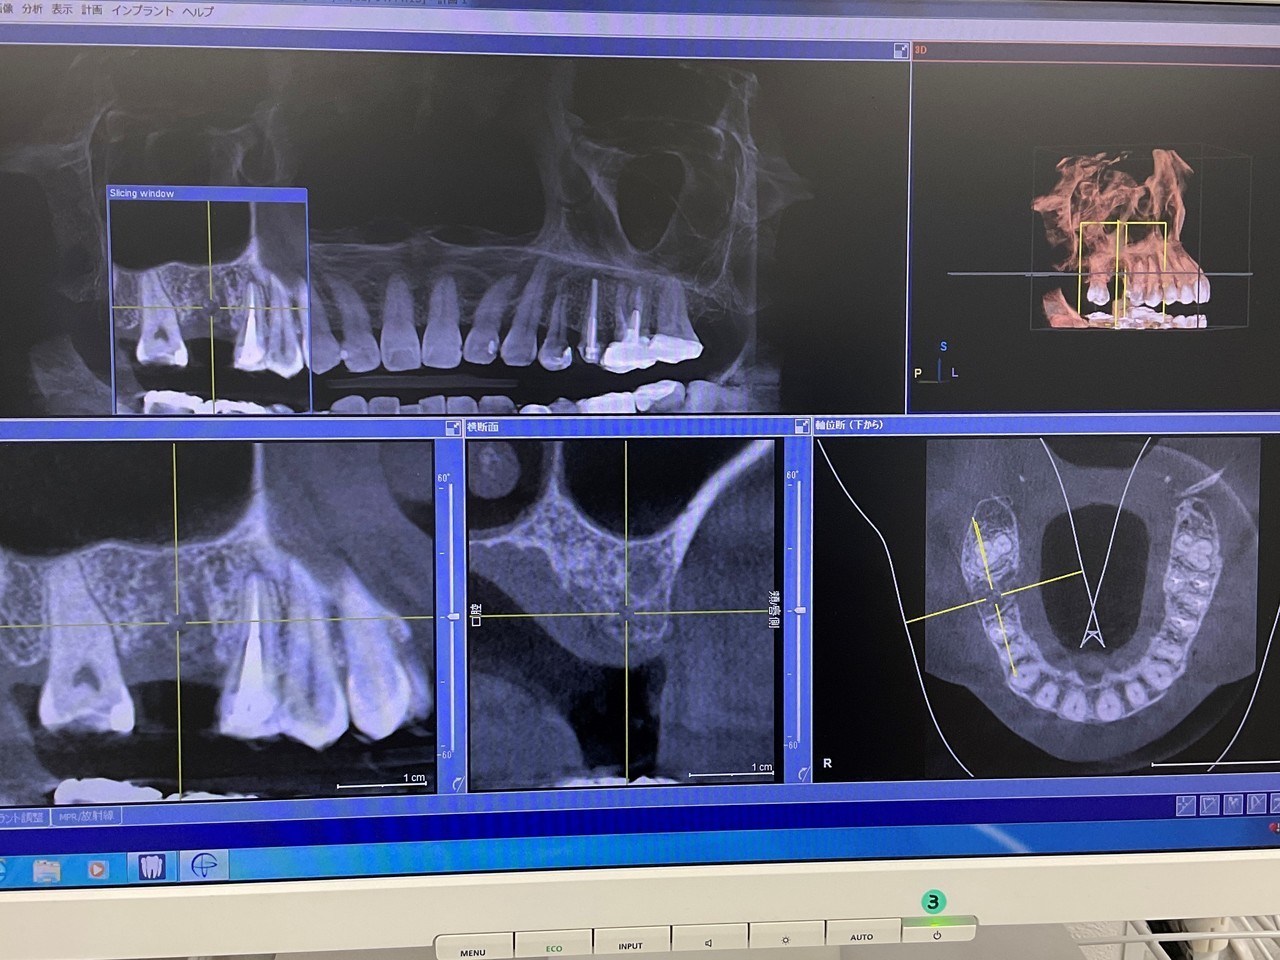

インプラント精密検査

CT撮影で立体的な顎の骨を確認できます。

CTシミュレーション

CTデータをインプラント解析ソフトに入れ、手術のシミュレーションをします。

・骨の状態を確認し、骨造成が必要か見極めます。

・シミュレーションでインプラントが可能か確認し、インプラントのサイズを調べます。

治療計画の説明

コンサルティングでシミュレーション結果を解説します。